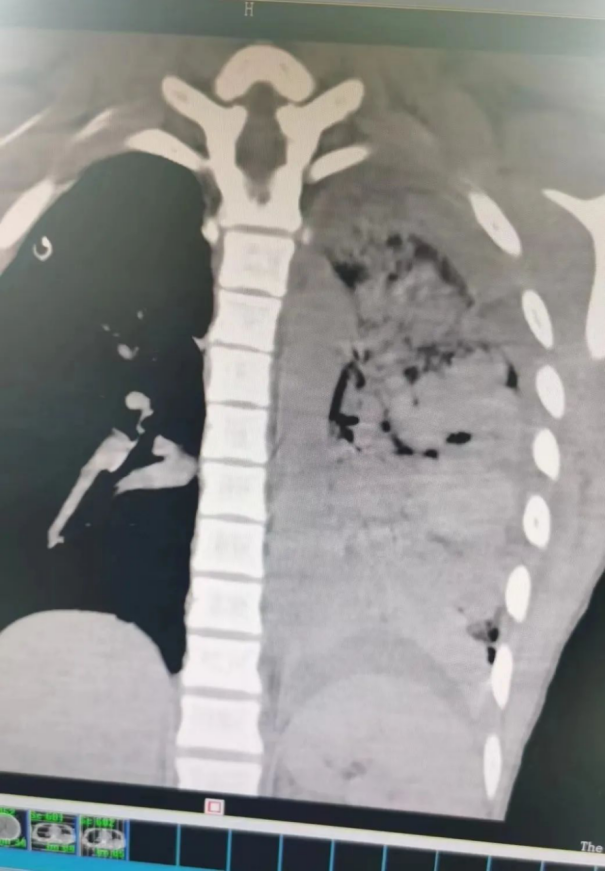

“先抢救,送往ICU!” 上午6时,患者被送往ICU,当时患者血压低、心率快、呼吸窘迫、血氧下降、右侧胸壁皮下气肿且进行性增大,气道持续引出大量鲜血,结合影像学和检验结果,诊断为肺挫伤、创伤性湿肺、右侧血气胸、左侧肋骨骨折、创伤性休克、创伤性凝血障碍、蛛网膜下出血、颅骨骨折。

▲ 胸部CT提示左肺挫伤出血